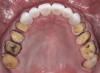

Fig 3. Preoperative occlusal view of maxillary arch.

Figure 3

A 40-year-old patient presented with the chief complaint: “My teeth are cracking, and I would like to have my original bite.” Dental findings included Class I occlusion with slight misalignment between teeth Nos. 8 and 9. Generalized severe occlusal wear and slight Class I mobility of teeth Nos. 23 to 26 were noted. Caries lesions were found on teeth Nos. 2, 4, 6, 8, 9, and 14 and abfraction lesions on teeth Nos. 4, 5, 10, 11, 13, 20, and 21. Figure 1 through Figure 3 depict the preoperative situation. Full-mouth rehabilitation was suggested. The goals for the restorative treatment were management of erosive etiology, conservation of tooth structure, and long-term protection of the restorations. A diagnostic wax-up was instrumental in determining functional and esthetic treatment goals and establishing new anterior guidance (Figure 4). A comprehensive, step-by-step treatment approach was applied, which, after periodontal pretreatment, caries control, and provisionalization, included definitive preparation (Figure 5) and restoration of the maxillary anterior teeth to establish anterior occlusal guidance. CAD/CAM–fabricated full-contour monolithic high-translucent zirconia crowns (Katana™ UTML Ultra Translucent Multi-Layered, Kuraray Noritake Dental, kuraraynoritake.com) were fabricated (Figure 6 and Figure 7) and cemented with self-adhesive resin cement (Panavia SA, Kuraray Noritake Dental). Figure 8 demonstrates the cemented anterior crowns and refined conservative preparations of posterior teeth, which were performed with minimal tooth-structure removal. High-translucent monolithic zirconia onlays and crowns were fabricated (Katana Zirconia UT, Kuraray Noritake Dental) (Figure 9 to Figure 12). The posterior restorations were adhesively bonded following the APC zirconia-bonding concept. APC-Step A involved air-particle abrasion with 50-μm aluminum oxide at 1.5 bar with a chairside microetcher (Figure 13), followed by application (APC-Step P, Figure 14) of a special ceramic primer (ClearfilTM Ceramic Primer, Kuraray Noritake) with adhesive phosophate monomers (MDP). Relative moisture and contamination control was achieved with cotton rolls and retraction cords. Rubber dam placement, which is always preferred, was difficult in this situation. The enamel surfaces of the abutment teeth were selectively etched (Figure 15) with 35% phosphoric acid (K-Etchant Gel, Kuraray Noritake Dental) and the dentin conditioned (Figure 16) with a self-etch dentin primer (Panavia V5 Tooth Primer, Kuraray Noritake Dental). A dual-cure adhesive resin (Panavia V5 Paste Universal, Kuraray Noritake Dental) was dispensed directly into the restorations with an automix syringe. The restorations were inserted, and excess cement was carefully removed (Figure 17 and Figure 18) before light polymerization (Figure 19). Postoperative views depict the treatment outcome (Figure 20 to Figure 22).